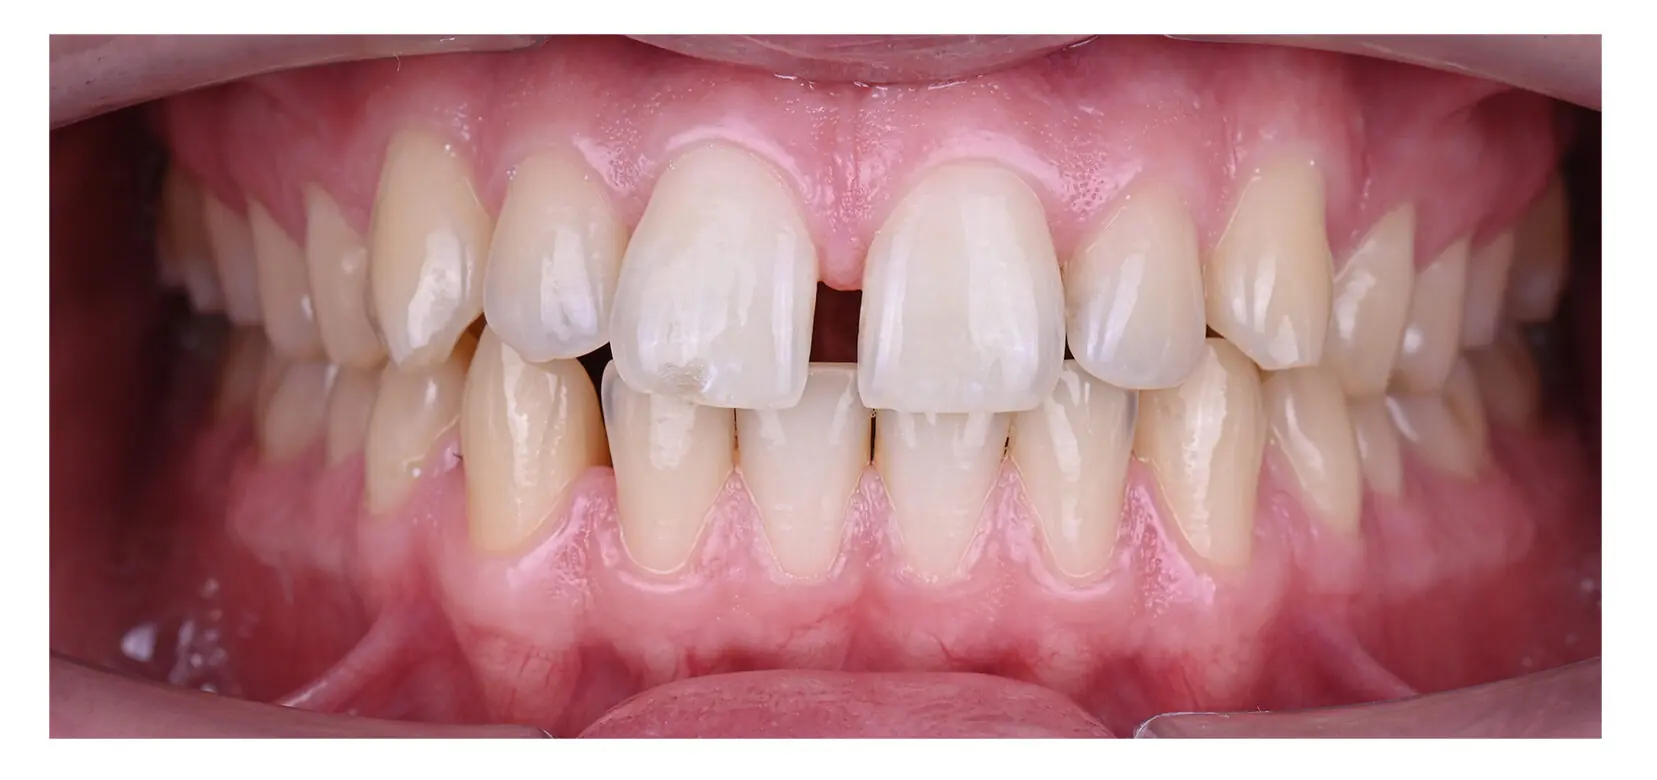

A gap between teeth, especially the front teeth, can be challenging to overcome. In addition to affecting appearance and self-confidence, this orthodontic issue can be damaging to overall oral health.

A diastema is a medical term that means the presence of a gap between two or more teeth. This condition occurs in both young and older people and can develop between any teeth. The midline diastema is the most common type and specifically refers to the gap between the two upper front teeth.

Even if gaps between teeth do not bother you, it is important to have a diastema checked by a dentist if it is caused by a more serious condition, such as gum disease. Gaps between teeth can also indicate that you have a misaligned bite, which can lead to chipping or breaking teeth.